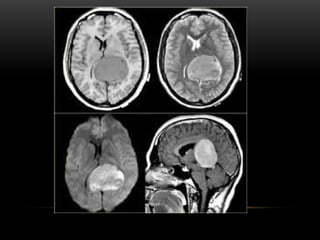

A primeira utilização operacional de um

tomógrafo computadorizado no mundo foi em

Atkinson Morley Hospital, em Londres, berço dos

estudos de Hounsfield. Além disso, o primeiro

equipamento de TC, só permitia a avaliação do

metabolismo cerebral ou de tumores do cérebro.

A primeira utilizaçãooperacional de um tomógrafo computadorizado no mundo foi em Atkinson Morley Hospital, em Londres, berço dos estudos de Hounsfield. Além disso, o primeiro equipamento de TC, só permitia a avaliação do metabolismo cerebral ou de tumores do cérebro.